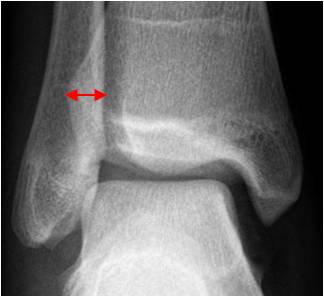

Sindesmosis tibioperonea:

En lesiones de la sindesmosis tibioperoneoastragalina, se produce ruptura de los ligamentos tibioperoneo anterior y posterior. En la Rx AP existe aumento del espacio entre la tibia y el peroné mayor de 6 mm. (29). (Fig 87 y 89).

Fig 87. Espacio tibioperoneo.

Rx AP. Espacio normal entre la tibia y el peroné.

Sombra tibioperonea:

El maleolo tibial lateral se superpone al peroné, entre 8 y 10 mm. (3). (Fig 88). Este espacio también disminuye, en la diastasis tibioperonea. (3). (Fig 89.).

Fig 88. Sombra tibioperonea.

Rx AP. Interposición normal del maleolo, sobre el peroné.

Fig 89. Lesión de ligamentos de la mortaja tibioperonea.

A: Rx AP. Aumento del espacio tibioperoneo y disminución de la sombra tibioperonea, lo que hace sospechar lesión ligamentaria.

B: TAC axial. Aumento del espacio tibioperoneo posterior, por lesión ligamentaria.